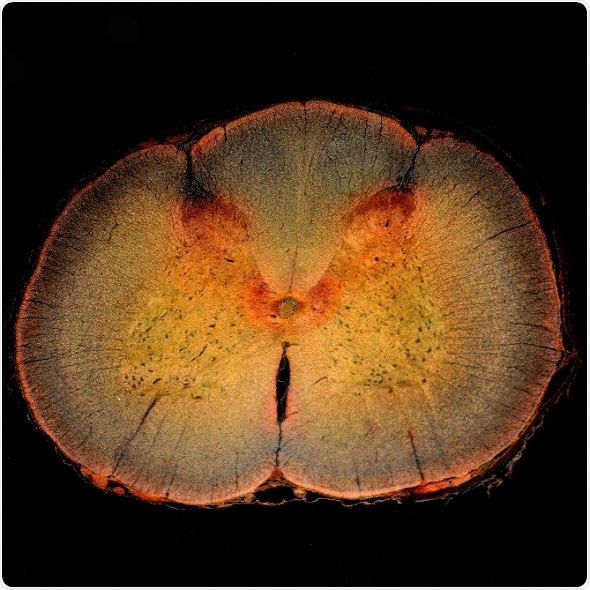

Spinal cord cross section, including the spinal cord dorsal horn, where pain is processed.

Credit: dw_ross/Flickr.